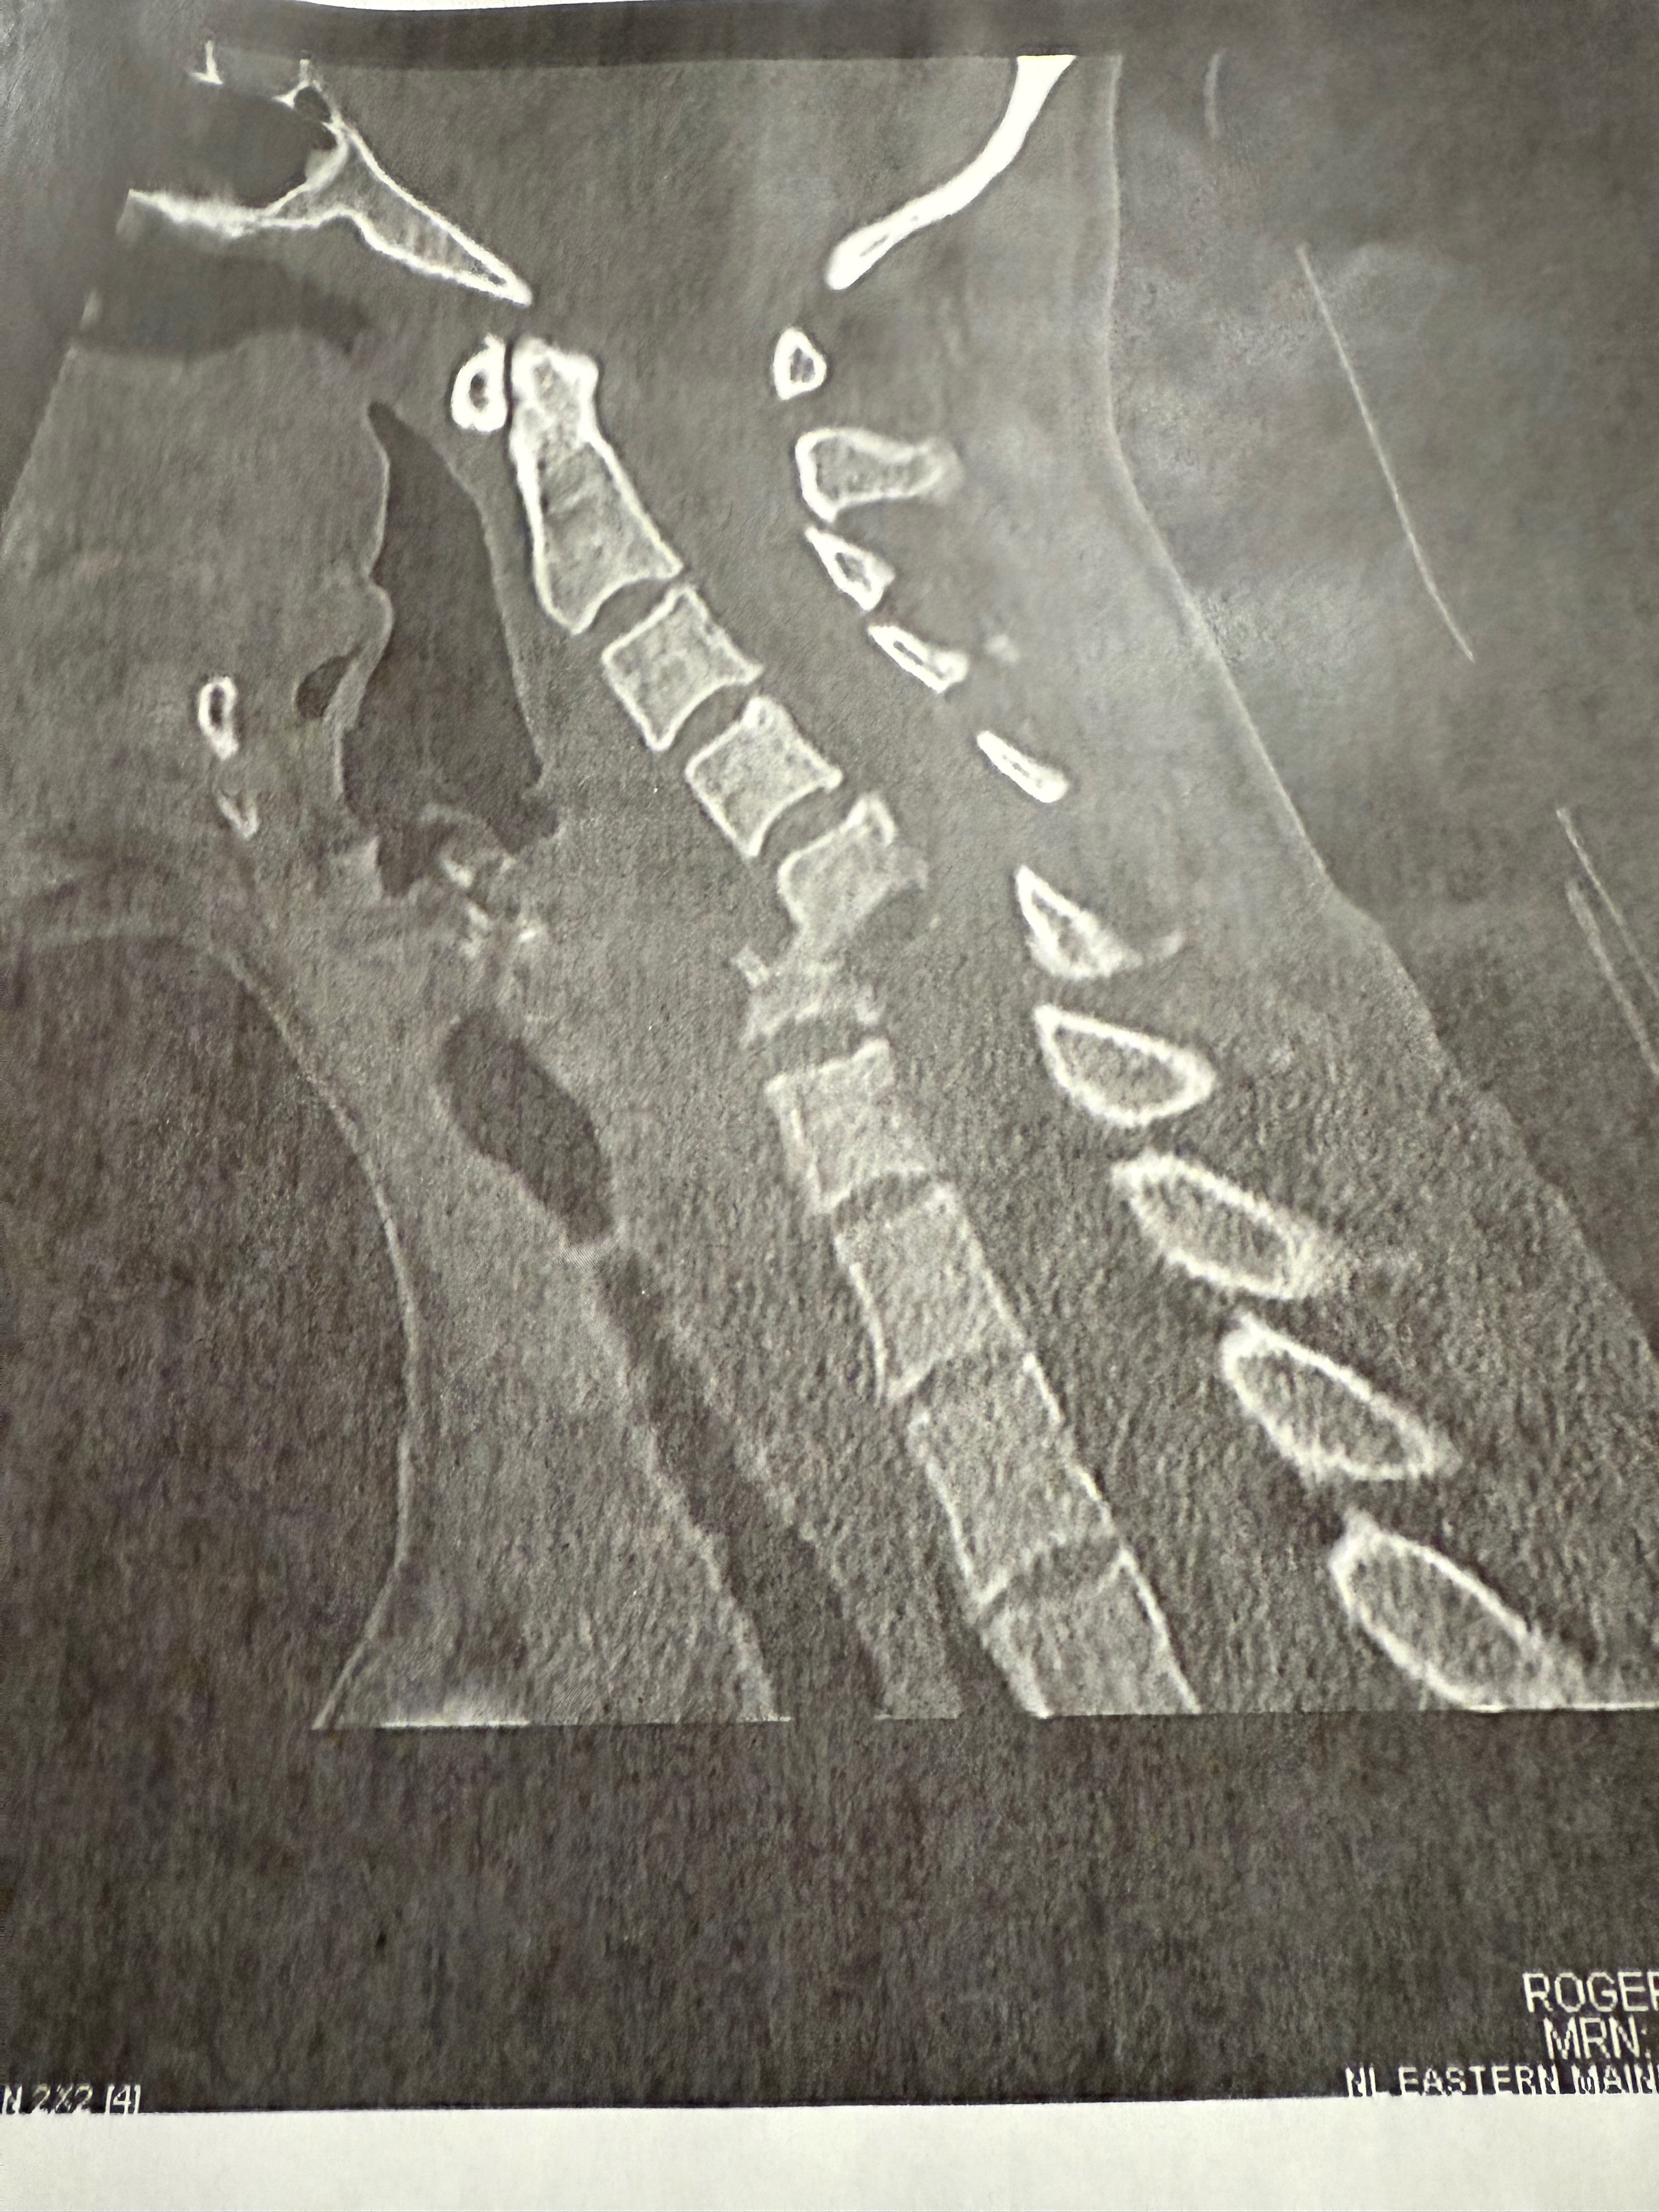

Rebecca is a mother of 2 young children, living in a 1 income household. After being shuffled around local health care facilities for over a month MRI imaging revealed a “complete collapse” of her C5+C6 bones in spinal column causing near full internal decapitation as well as infection. Immediate emergency surgery was needed upon hospital admission, with the only other outcome being unfortunate death. 2 spinal surgeries, 6 weeks of IV antibiotics via PIC, physical therapy and months of intensive care/healing leaves Rebecca inpatient with a discharge date that is yet TBD and unable to work for 4 to 6 months. The only income for the entire household has already suffered a massive financial cut through the holidays